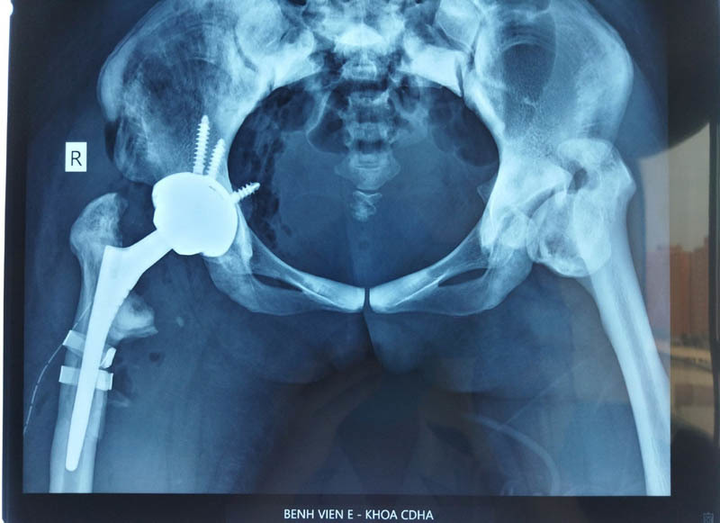

Phim Xquang của bệnh nhân sau mổ.

9h sáng ngày 26/10, bệnh nhân được gây mê. Quá trình mổ diễn ra đầy khó khăn như các bác sĩ dữ liệu. “Mặc dù kéo giãn nhưng chi bệnh nhân vẫn co rất nhiều, chảy máu khá nhiều. Đặc biệt, quá trình cưa cổ xương đùi cũ của bệnh nhân cũng rất khó khăn. Mật độ xương đặc, mặc dù dự trù các lưỡi cưa sắc nhất, mới nhất nhưng vẫn bị hỏng cưa. Chúng tôi phải thay lưỡi cưa mới”, BS Hiếu nói thêm.

Quá trình phẫu thuật, 1 trong 2 thành xương bị gãy. Đây là điều không quá bất ngờ, vì ekip phẫu thuật đã xác định từ trước. Sau khi đặt xong chuôi khớp trong ống tủy xương đùi, dùng dụng cụ cố định lại phần xương gãy, đặt lại khớp, cuộc phẫu thuật mới kết thúc khi kim đồng hồ vượt quá 12h30.

“Cải thiện nhìn thấy rõ là 2 chân bằng nhau, thậm chí chân mổ dài hơn một chút. Khớp háng bên kia của bệnh nhân cũng hỏng, dự kiến sẽ phải mổ tiếp, như vậy 2 chân bệnh nhân mới có thể bằng nhau”.